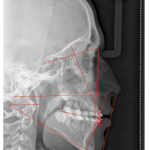

• A través de sencillas pero poderosas herramientas se pueden hacer trazados cefalométricos que permitan al médico observar, analizar y/o diagnosticar detalladamente y con mayor rapidez y confiabilidad.

- Steiner